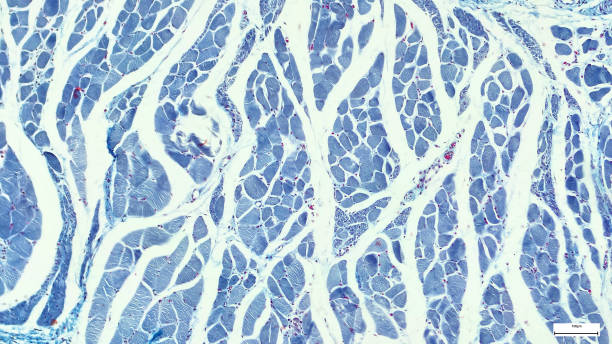

Según ha informado el CSIC, «la senescencia celular es un proceso por el cual una célula dañada entra en un estado de reposo, sin dividirse, pero desencadenando señales que permitan a las células vecinas conocer el daño y promover la reparación del tejido».

De este modo, añaden que «este mecanismo es muy eficaz a corto plazo, sin embargo, su acumulación a lo largo de la vida provoca la aparición de otras enfermedades crónicas asociadas con el envejecimiento”.

Igualmente, el investigador del Centro Nacional de Biotecnología en el CSIC, Manuel Collado, ha dicho que “muchas veces denominadas células zombis, las células senescentes contribuyen al deterioro asociado a la edad y hoy en día constituyen un objetivo de la industria farmacéutica, que ve en su eliminación un posible remedio frente a enfermedades dispares, pero que tienen en común su asociación con la edad”.